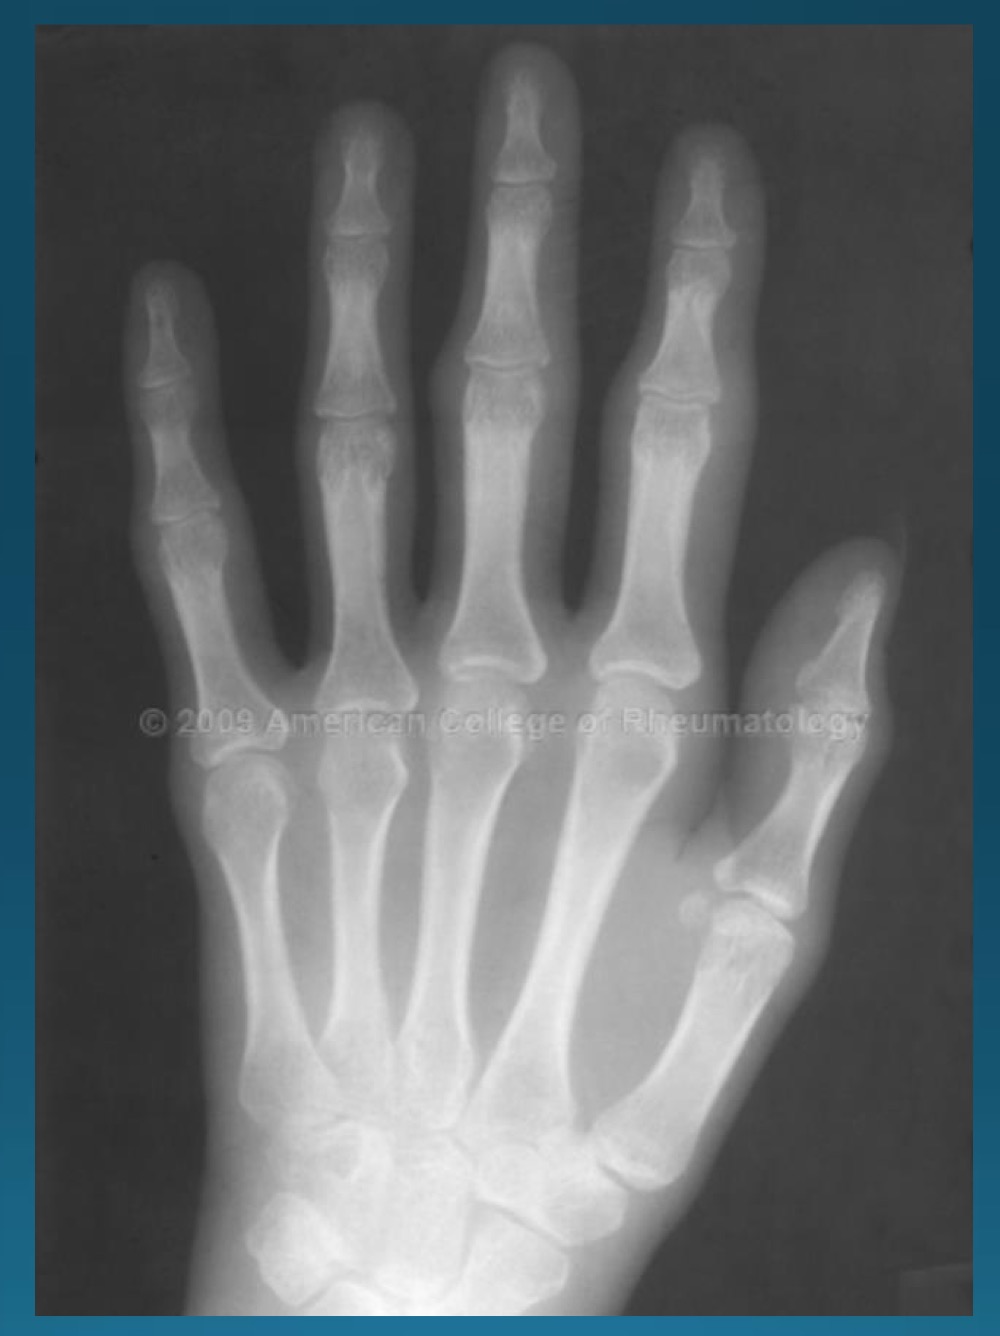

what are the findings in this image?

erosive osteoarthritis

waht are the features denoting erosive osteoarthritis on radiograph?

central erosions creating gull wing sign

EOA likes what joints?

DIP, PIP, 1st CMC